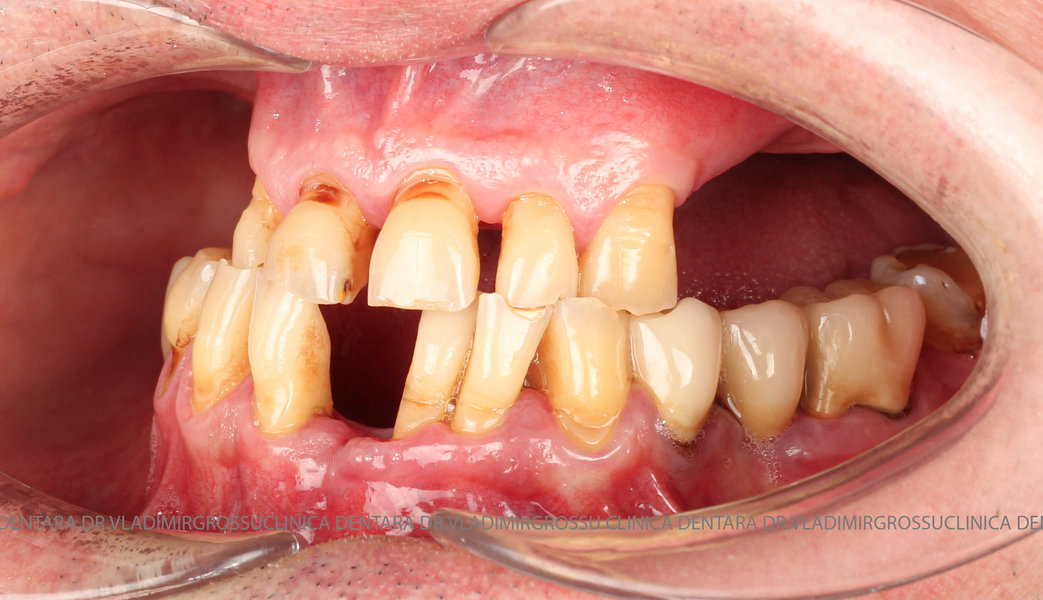

Cazuri clinice conceptul All-on-6